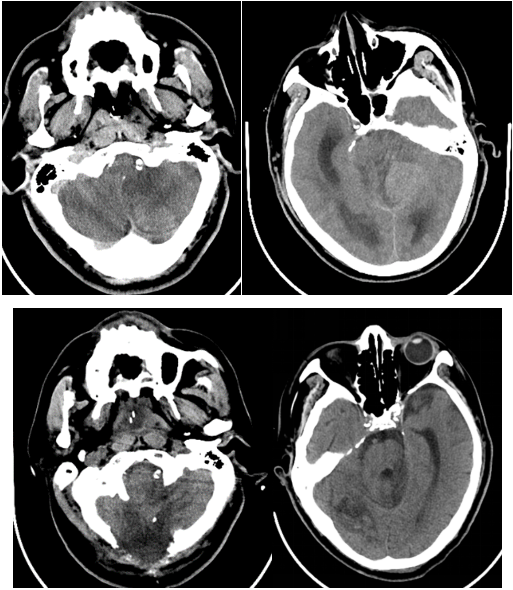

术后患者先后出现急性脑水肿、肺感染、急性肾功能不全等合并症。每一种情况可能导致患者病情恶化,甚至危及生命。高建瓴主任带领的重症医学团队对患者进行全方面评估,给患者拟定最佳治疗方案:呼吸机辅助通气、抗生素抗感染同时纤维支气管镜肺泡灌洗治疗、床旁连续性血液滤过,同时给予甘露醇、白蛋白、速尿等脱水降低颅内压等治疗。

术后第四天患者出现了严重脑水肿-脑疝形成。神经外科黄煜伦主任带领神经外科团队评估后急诊行脑室外引流装置植入术+后颅凹去骨瓣减压术。